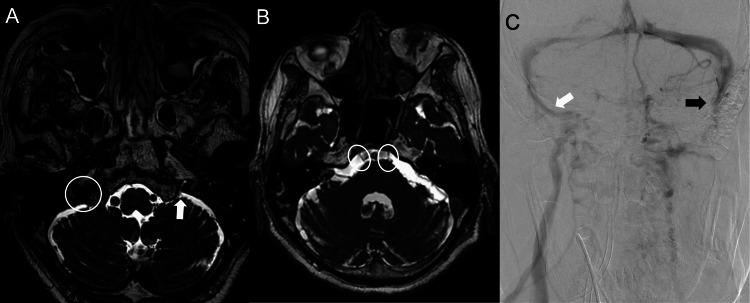

We present a rare case of clival fracture in which the patient presented with multiple lower cranial nerve palsy (similar to Vernet syndrome or Collet-Sicard syndrome). Multiple lower cranial nerve palsy from skull base lesions includes Vernet syndrome and Collet-Sicard syndrome. Clival fracture is a rare condition, and the optimal treatment method has yet to be established. A 73-year-old man fell down a flight of stairs and was diagnosed with injuries such as traumatic intracranial hemorrhage, clival fracture, and facial bone fracture. The patient presented with bilateral cranial nerve VI, IX, X, XI, and right XII palsies caused by clival fracture but no instability at the craniocervical junction, so we performed external fixation using a halo device. The patient developed delirium in the subacute phase, which was considered to be aggravated by the halo device. We therefore safely removed the halo device on hospital day 54 after confirming porosis of the fractured clivus on computed tomography. The patient did not complain of neck pain, and paralyses of cranial nerves VI and XII had completely resolved, while those of cranial nerves IX, X, and XI had also improved, so the patient could start direct swallowing training. Clival fracture with bilateral multiple cranial nerve palsies similar to Vernet syndrome or Collet-Sicard syndrome is highly rare. Accordingly, no standard treatment has been established. A halo device can be an effective treatment for clival fracture, and the duration of fixation could be determined flexibly based on the condition of each case.

摘要

我们报告一例罕见的斜坡骨折病例,该患者表现为多发性低位颅神经麻痹(类似于韦尔内综合征或科莱-西卡尔综合征)。由颅底病变引起的多发性低位颅神经麻痹包括韦尔内综合征和科莱-西卡尔综合征。斜坡骨折是一种罕见疾病,最佳治疗方法尚未确定。一名73岁男性从一段楼梯上摔倒,被诊断为创伤性颅内出血、斜坡骨折和面部骨折等损伤。该患者因斜坡骨折出现双侧颅神经VI、IX、X、XI及右侧XII麻痹,但颅颈交界处无不稳定情况,因此我们使用头环装置进行了外固定。患者在亚急性期出现谵妄,认为是头环装置加重了病情。因此,在计算机断层扫描确认骨折斜坡骨质疏松后,我们于住院第54天安全拆除了头环装置。患者未诉颈部疼痛,颅神经VI和XII的麻痹已完全缓解,而颅神经IX、X和XI的麻痹也有所改善,因此患者可以开始直接吞咽训练。类似于韦尔内综合征或科莱-西卡尔综合征的双侧多发性颅神经麻痹的斜坡骨折极为罕见。因此,尚未确立标准治疗方法。头环装置可为斜坡骨折提供有效治疗,固定时间可根据具体情况灵活确定。